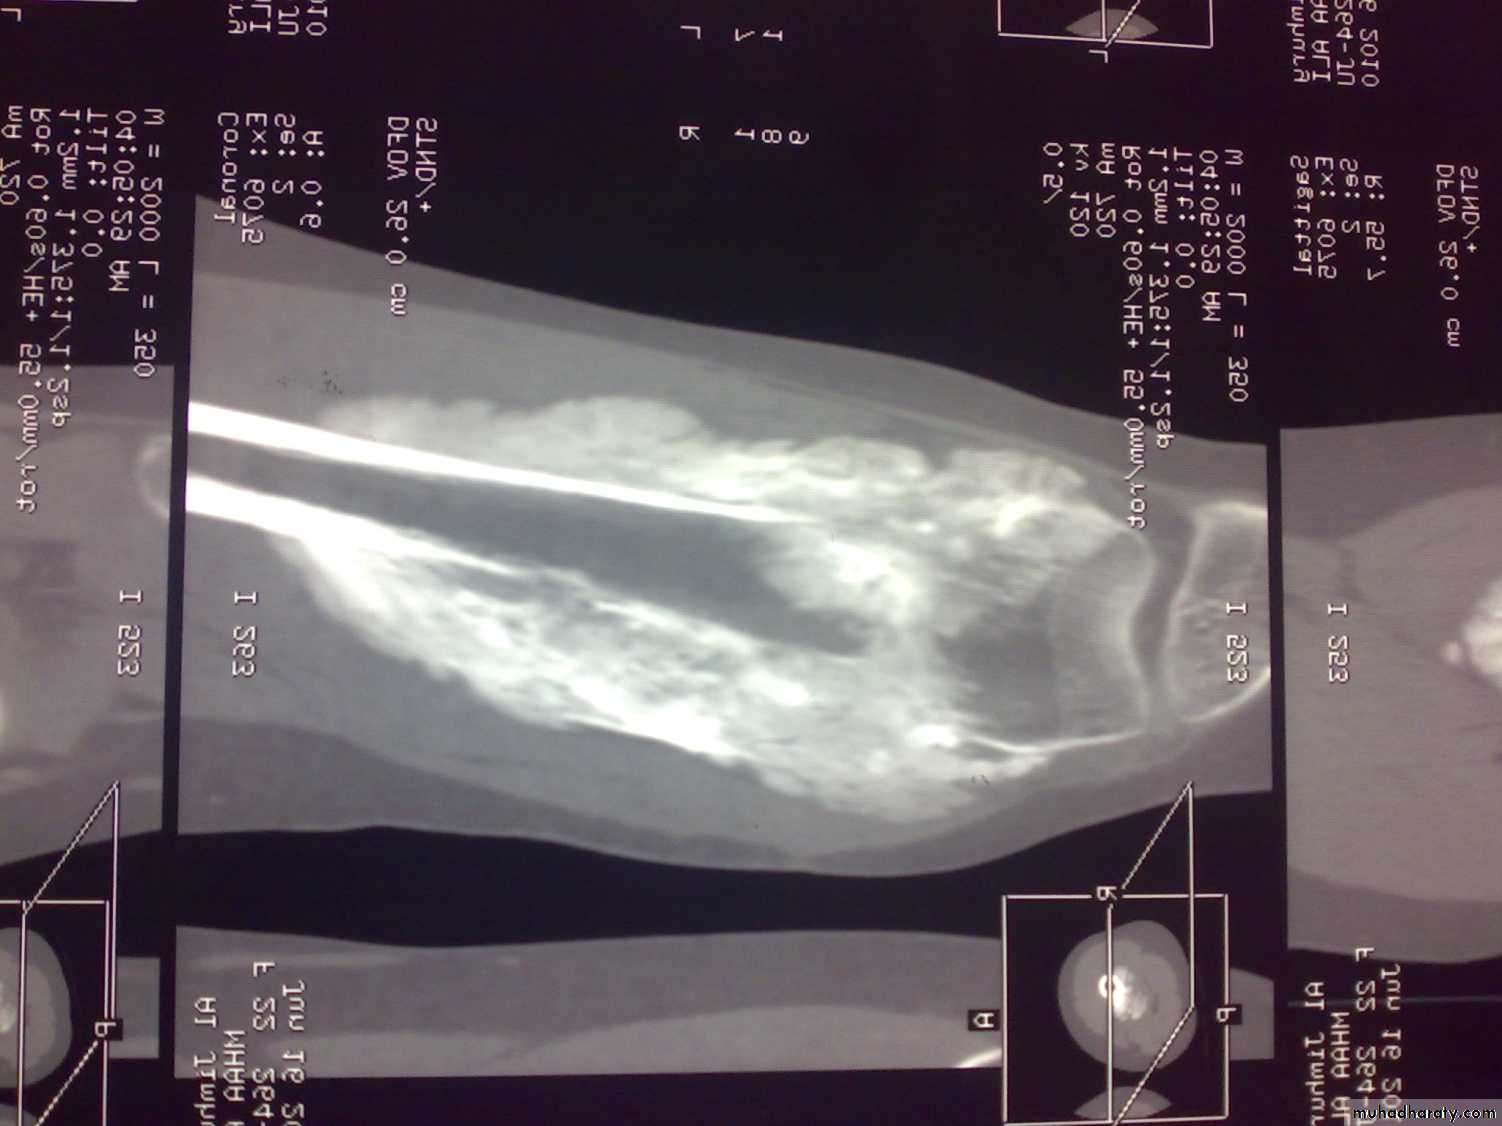

C-T of shoulderMRI

Reading of radiofrequency emissions from atoms and molecules of tissues exposed to static magnetic field.

Indications:

Bone tumors; size and spread.

MRI of osteosarcoma of femur